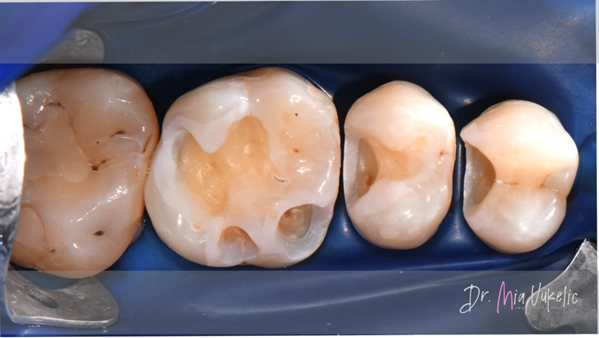

Voor het herstel van de approximale wand werden Halo™-matrixbanden en een Halo™-ring van Ultradent Products gebruikt.

Na het herstellen van de approximale wand werd de restauratie verder laagsgewijs, van buiten naar binnen opgebouwd. De eerste stap bestond uit het aanbrengen van een laag flowable composiet met een dikte van 0,5 mm (Tetric EvoFlow™, Ivoclar*).

Het materiaal dat voor de restauratie werd gebruikt, was Transcend™-composiet (Ultradent Products). De approximale wand werd vervaardigd met de kleurtint EW en de twee daaropvolgende horizontale lagen met de kleurtint A3D. Individuele karakterisering werd verkregen door inkleuring met Kolor + Plus™ kleurmodificator - bruin (Kerr*).

Na het polijsten kreeg de vulling een verzegeling (PermaSeal™-composietsealer, Ultradent Products). Tot slot werd de occlusie gecontroleerd en werden röntgenopnamen gemaakt.

Zoals te zien is op de foto’s van het eindresultaat, zorgt Transcend-composiet voor een zeer esthetische restauratie. Het sectionele matrixsysteem Halo leverde een uitstekende approximale anatomie, wat bleek uit de röntgenopname.